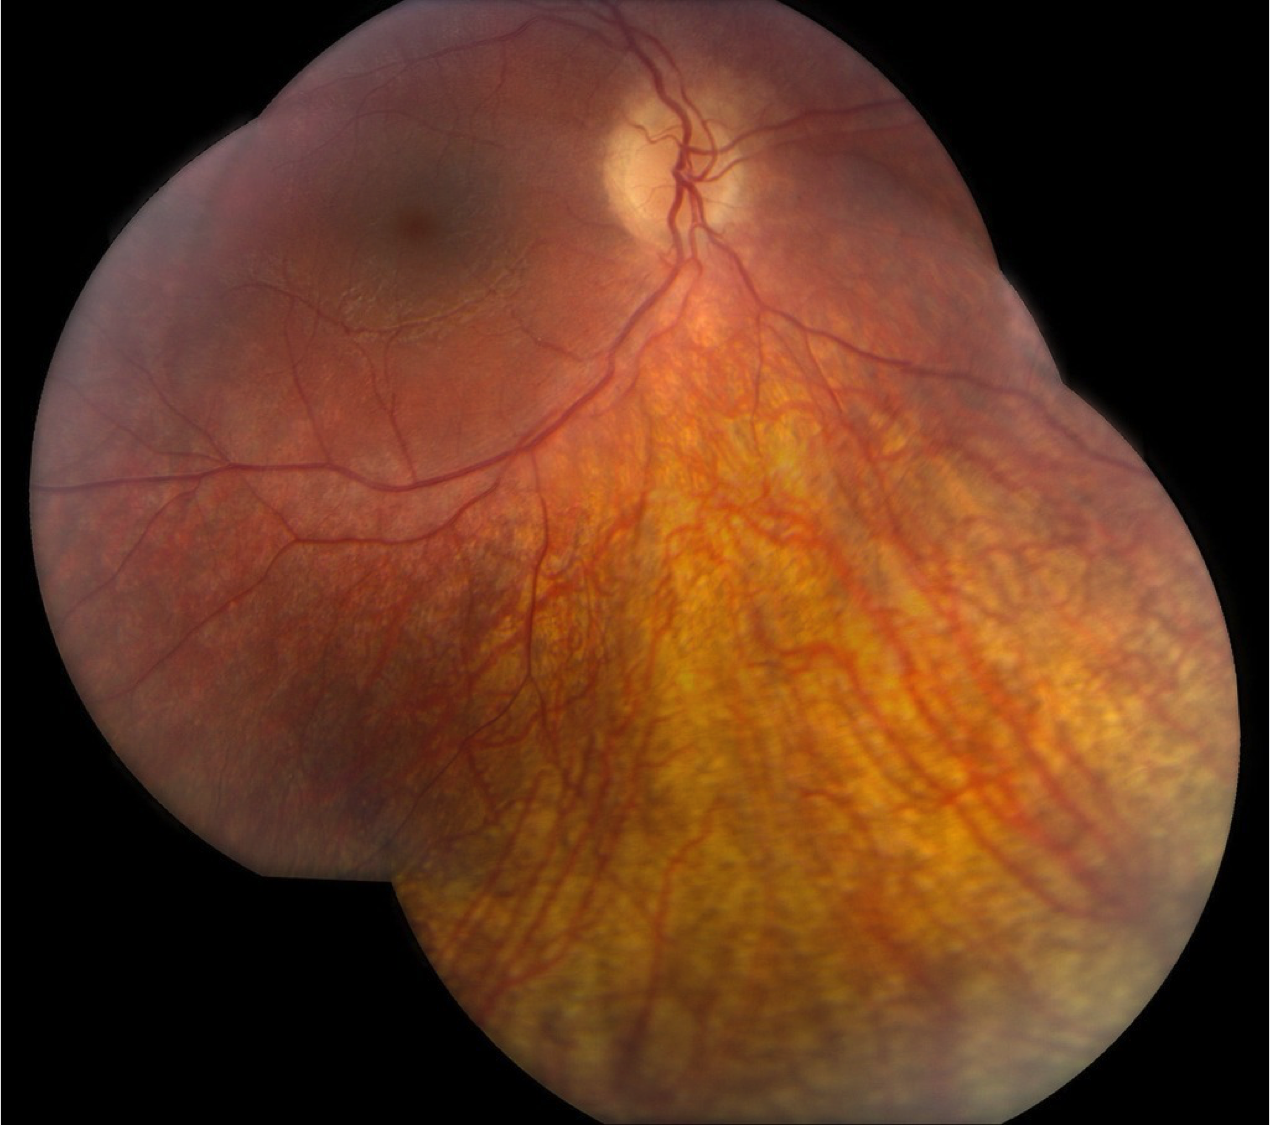

Case 13 is a 15 year old male was noted to have abnormal vision at 3 months of age. He had large amplitude nystagmus, did not respond to his parents faces and would not follow any type of toy or light that was put in front of him. His pupils constricted when the room lights were turned off and dilated when they were turned on. Retinoscopy revealed over seven diopters of hyperopia and electroretinography detected no responses under any stimulus conditions. The best acuity ever recorded has been bare light perception. His parents have normal vision.

Color fundus photograph of the right eye.